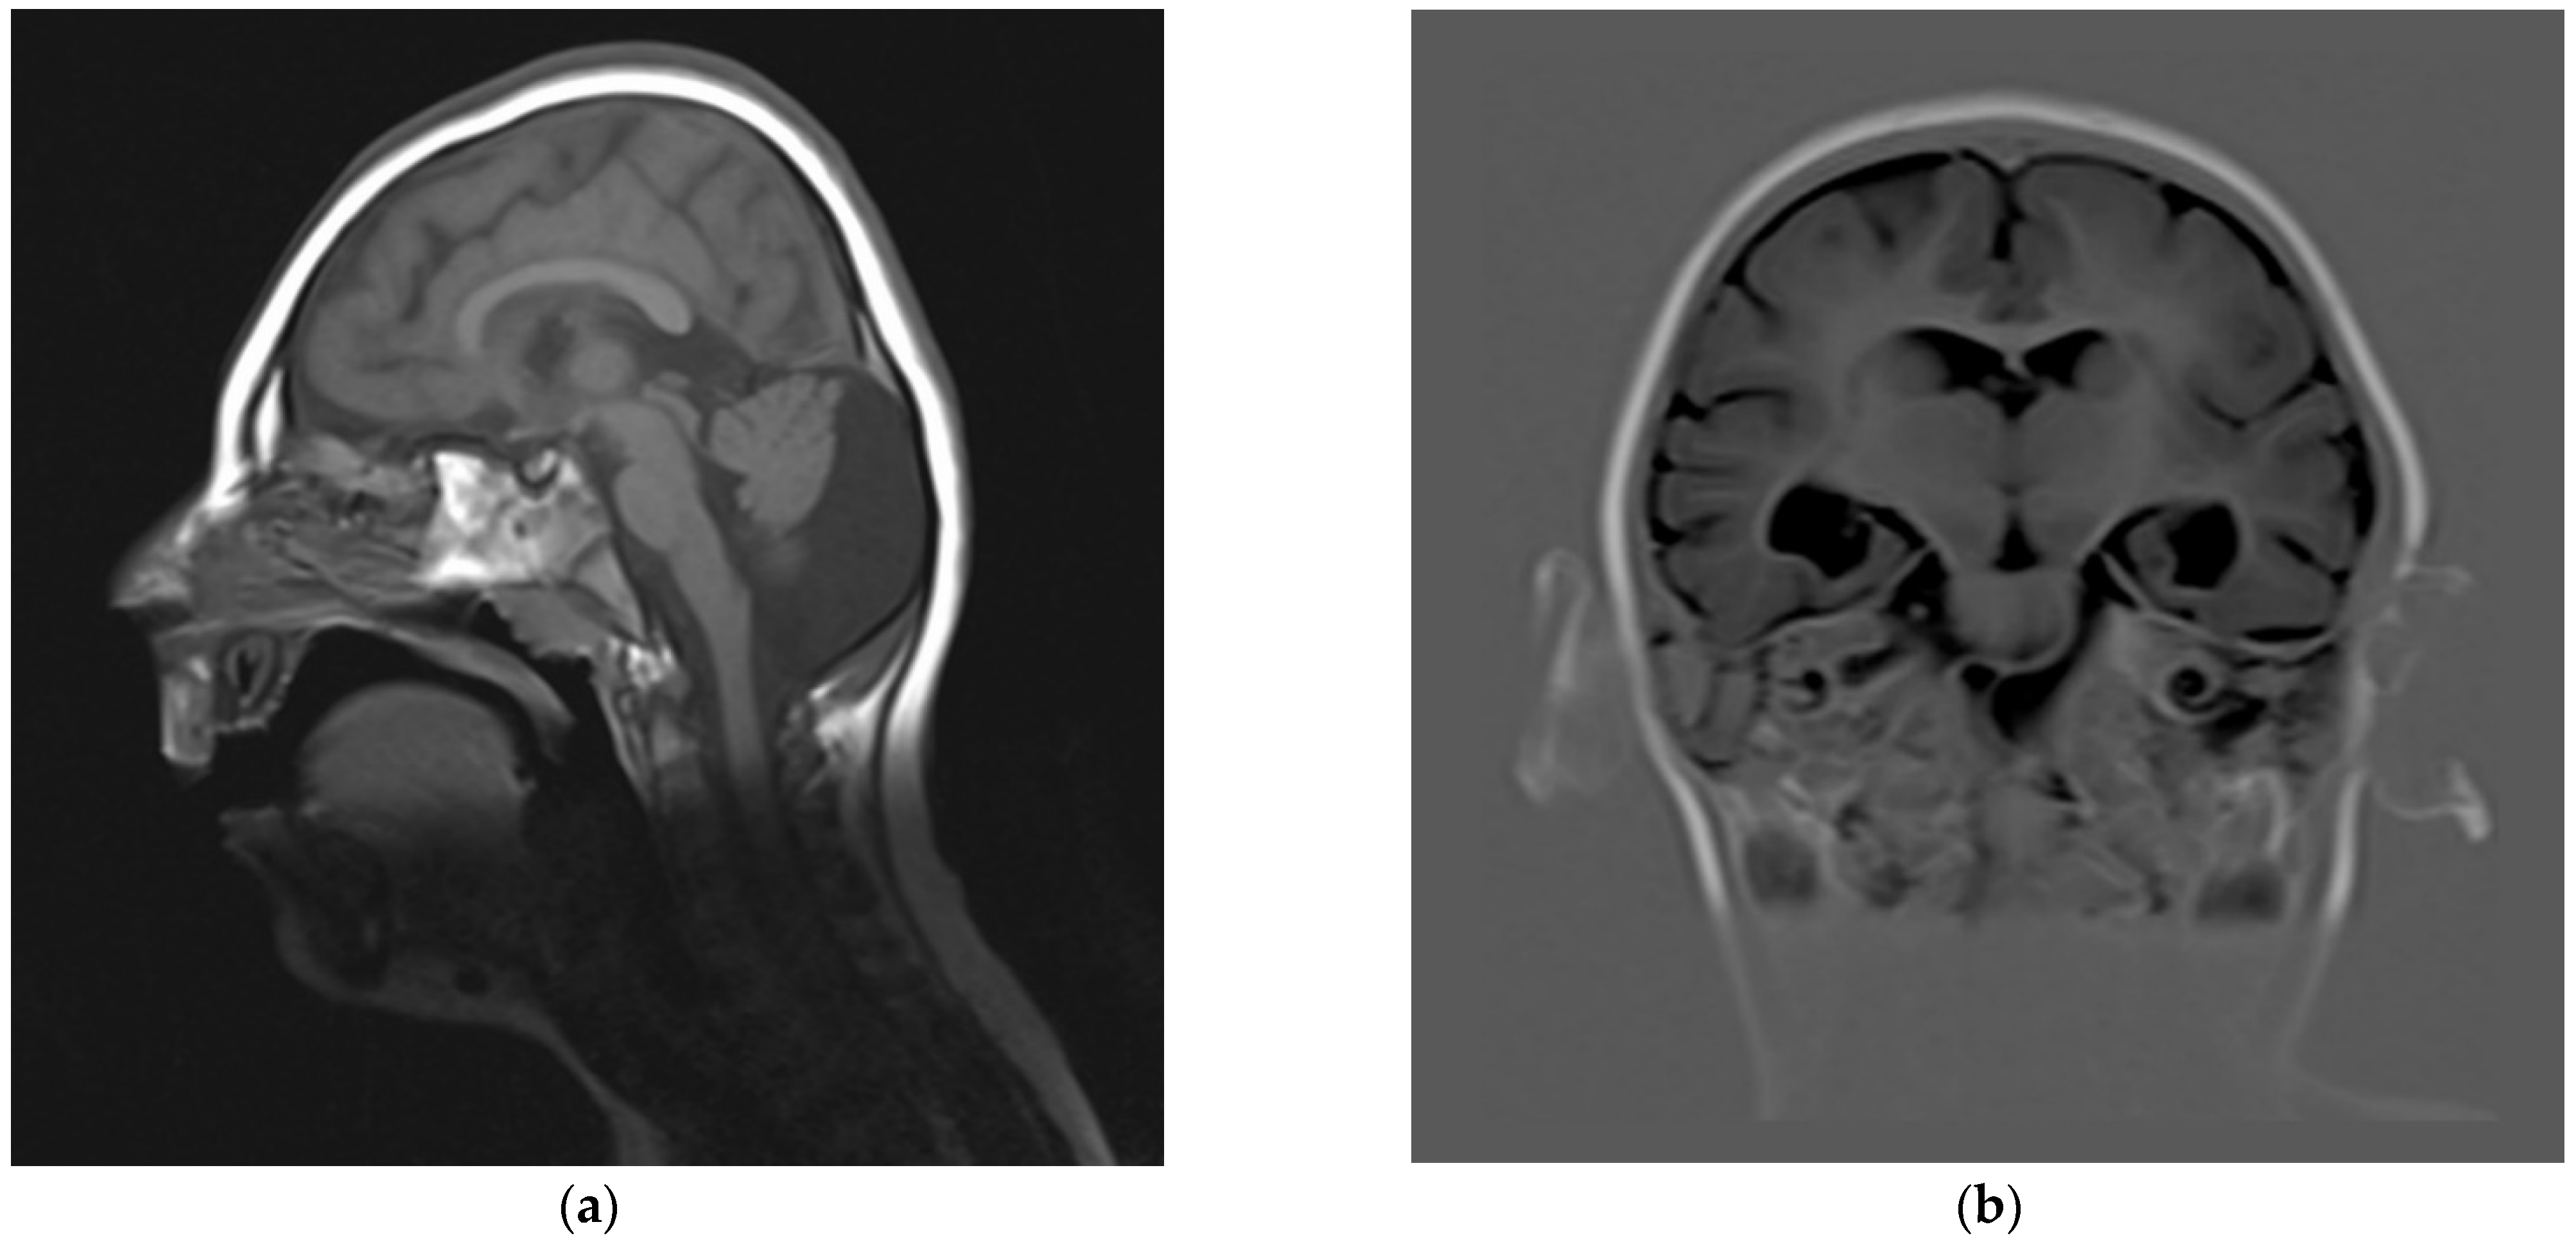

| This report | 1 | del ex 1−8 | −3.5 | −5 (10 y) | −2 | mild DD, profound ID (no language) | fronto-polar simplified gyral pattern, PNH, mild ventriculomegaly, enlarged posterior fossa | sloping forehead, highly arched eyebrow, exotropia, epicanthus, large ears; hyperactivity | Pakistani (northeast) |